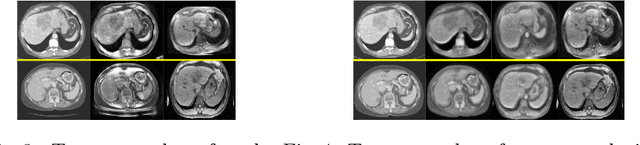

Abstract:Deep neural networks have shown exceptional learning capability and generalizability in the source domain when massive labeled data is provided. However, the well-trained models often fail in the target domain due to the domain shift. Unsupervised domain adaptation aims to improve network performance when applying robust models trained on medical images from source domains to a new target domain. In this work, we present an approach based on the Wasserstein distance guided disentangled representation to achieve 3D multi-domain liver segmentation. Concretely, we embed images onto a shared content space capturing shared feature-level information across domains and domain-specific appearance spaces. The existing mutual information-based representation learning approaches often fail to capture complete representations in multi-domain medical imaging tasks. To mitigate these issues, we utilize Wasserstein distance to learn more complete representation, and introduces a content discriminator to further facilitate the representation disentanglement. Experiments demonstrate that our method outperforms the state-of-the-art on the multi-modality liver segmentation task.